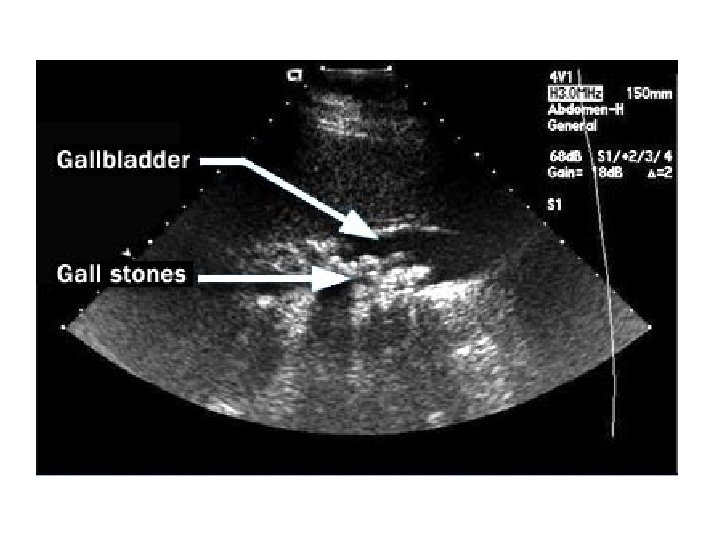

Gallbladder Stones

Gall stones

Gallstones